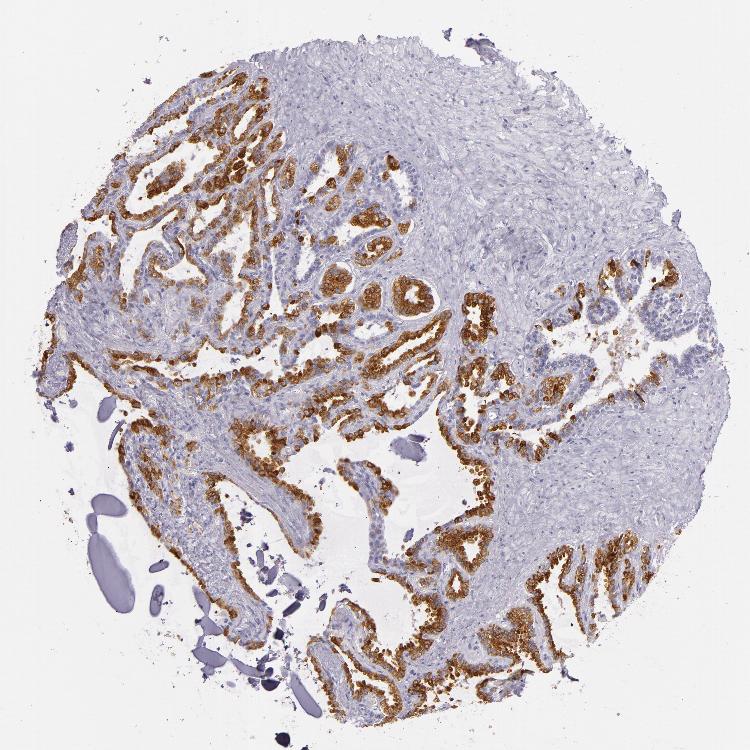

SEMINAL VESICLE - Antibody stainingi

Antibody staining in the annotated cell types in the current human tissue is reported as not detected, low, medium, or high, based on conventional immunohistochemistry profiling in selected tissues. This score is based on the combination of the staining intensity and fraction of stained cells.

Each image is clickable and will lead to virtual microscopy that enables deeper exploration of all samples and also displays staining intensity scores, fraction scores and subcellular localization as well as patient and tissue information for each sample.

Antibody CAB002165

Glandular cells High